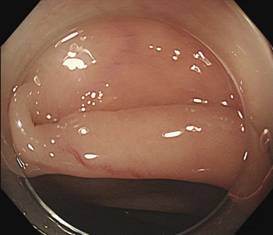

陈先生28岁,主诉间断腹胀1月余,肠镜检查于横结肠发现息肉样病变,表面正常黏膜覆盖、充血,靠近根部可见扩张血管。

结肠黏膜-黏膜下拉长型息肉是由黏膜黏膜肌层、黏膜下层构成的细长有蒂型的大肠息肉,是一种相对少见的非肿瘤性病变,病因不明确。